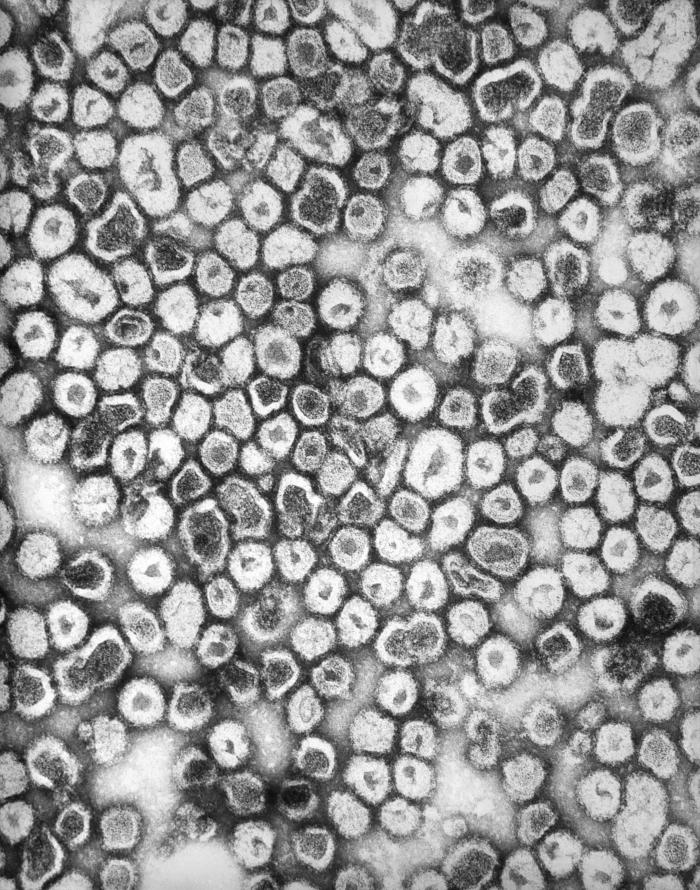

La Crosse virus. Centers for Disease Control and Prevention.